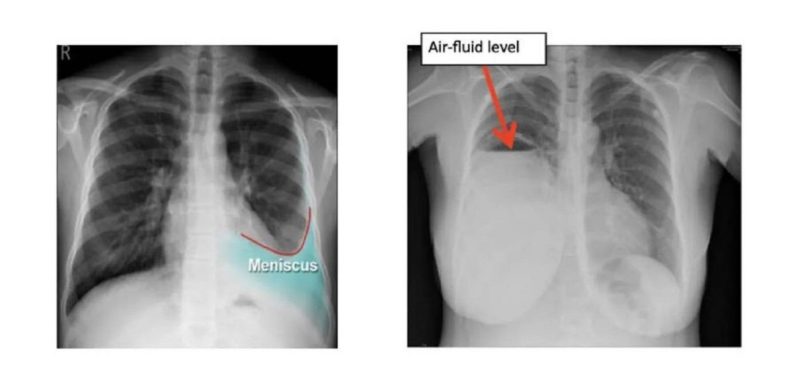

ในกลุ่มที่สองเกิดจากตัวปอดเอง (Exudative Pleural Effusion) ซึ่งมักจะเกิดจากมะเร็ง (เช่น มะเร็งปอด, มะเร็งเต้านมกระจายมาที่เยื่อหุ้มปอด), วัณโรคปอด (Tuberculosis), ปอดติดเชื้อ (Pneumonia) อันเกิดจากเยื่อหุ้มปอดอักเสบหรือมีการอุดตันของระบบน้ำเหลือง รวมถึงของเหลวที่มีโปรตีนสูงและเซลล์อักเสบจำนวนมาก โดยการรักษานั้น หากเกิดจากมะเร็งเราสามารถเอาน้ำออกแล้วใส่ยาเคลือบปอดเพื่อป้องกันการกลับมาเป็นซ้ำได้ (chemical pleurodesis) และในส่วนของกลุ่มที่เกิดภาวะติดเชื้อ เช่น วัณโรคหรือปอดติดเชื้อ หากดำเนินการรักษาแก้อาการของตัวโรค โดยลดอาการบวมน้ำลง อาการก็มักจะดีขึ้นตามมา แต่อาการที่พบในผู้ป่วยอยู่บ่อยครั้ง เช่น มีอาการหายใจลำบาก, มีภาวะเจ็บหน้าอก (โดยเฉพาะเวลาหายใจลึก ๆ) หรือไอแห้ง ๆ มีน้ำเสียงลดลง เหล่านี้แพทย์มักจะวินิจฉัยว่าเกิดจากน้ำในเยื่อหุ้มปอด ซึ่งสามารถใช้การเอกซเรย์ทรวงอก, อัลตราซาวด์ หรือ CT scan และอาจมีการเจาะน้ำในเยื่อหุ้มปอด เพื่อนำไปตรวจหาสาเหตุที่แน่นอน